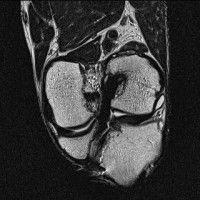

무릎 mri 간단히 봐주실 수 있으시나요 ㅠㅠ

안녕하세요 8년전 십자인대 수술하고 최근 무리한 운동에 무릎 불편감이 생겨서

mri 찍었습니다.

진단결과는 첫 찍은 병원에서 활액막염 이라는 진단을 받았습니다. 혹시 봐주실 수 있으실까요?

올라온 MRI가 단편적이라서 정확한 진단에 어려움이 있지만 십자인대에는 큰 이상이 있지는 않은것 같으며, 무릎관절내 물이 있는 것으로 보아 활액막염의 진단이 맞을 것 같습니다.

하지만 단편적인 영상이기 때문에 촬영병원에서 정확한 판독지 등을 받으시는 것이 좋겠습니다.